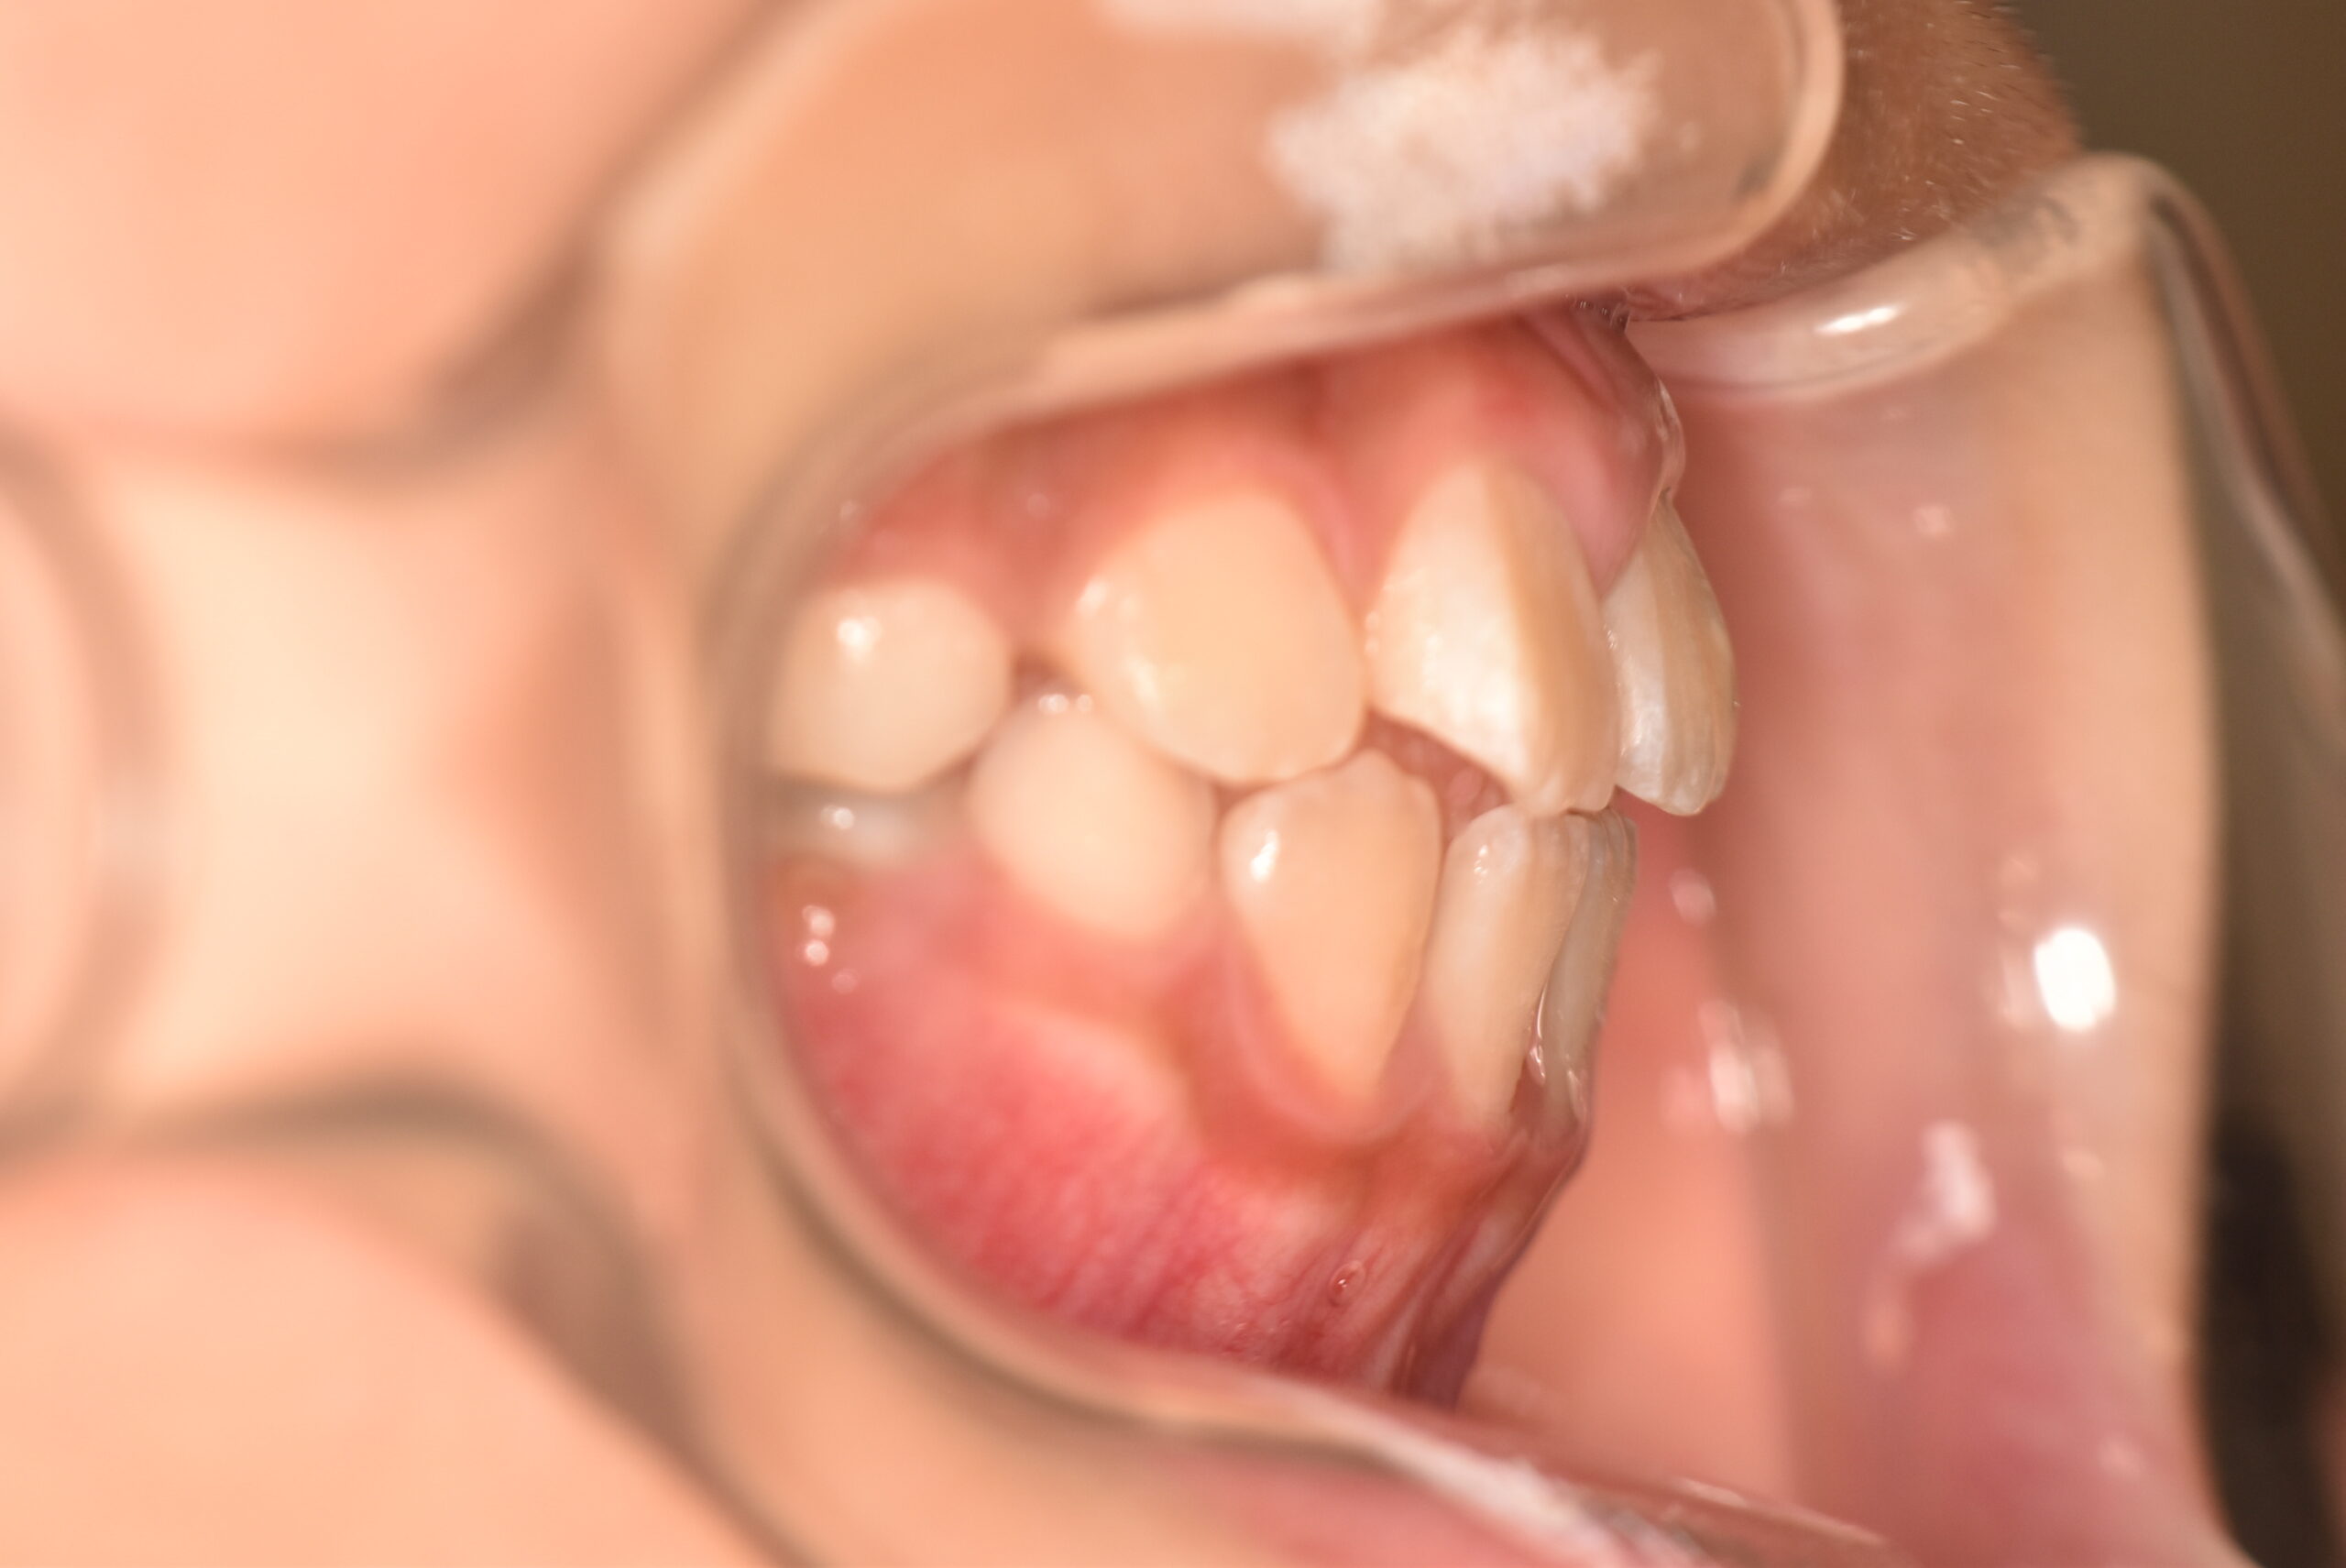

インビザラインファースト 【2724】

初診時

症例 症例 症例 症例

年齢

8歳 性 別 女性

治療期間 6ヶ月 費 用 矯正施術料:800,000円

調整料:4,000円/月

治療内容の詳細 初診時8歳の女児で、正中のズレを気にされ来院されました。

検査の結果、臼歯部交叉咬合を伴うアングルⅠ級不正咬合と診断しました。

治療としてはマウスピース矯正(インビザラインファースト)で配列を行い、上顎の側方拡大と萌出スペースを確保しました。

治療期間は、6ヶ月でした。

今後、側方歯生え変わりまで経過観察を行います。